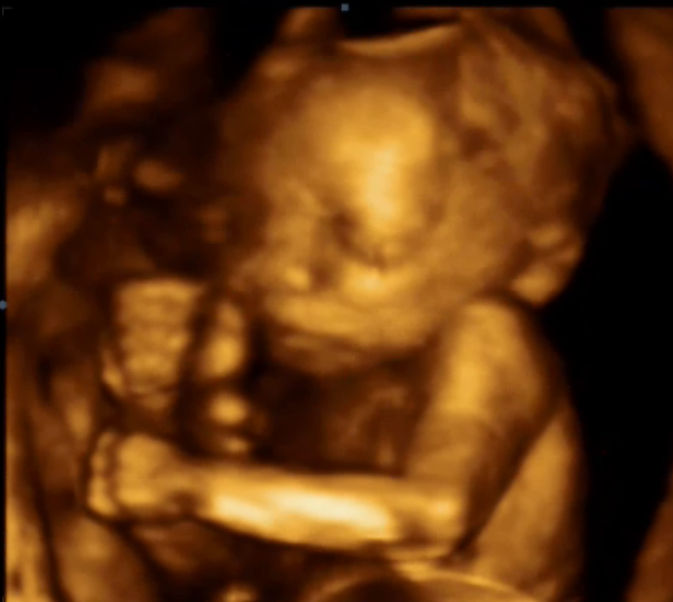

- 24. týden těhotenství je nejvhodnější k pořízení 3D fotky plodu. Většina plodů dává před obličej ručky nebo je natočena k sondě zády, proto se nemusí fotka podařit ihned, z velké většiny však 1x za těhotenství hezký obrázek získáme! Fotky lze vytisknout nebo sdílet přes Fetview